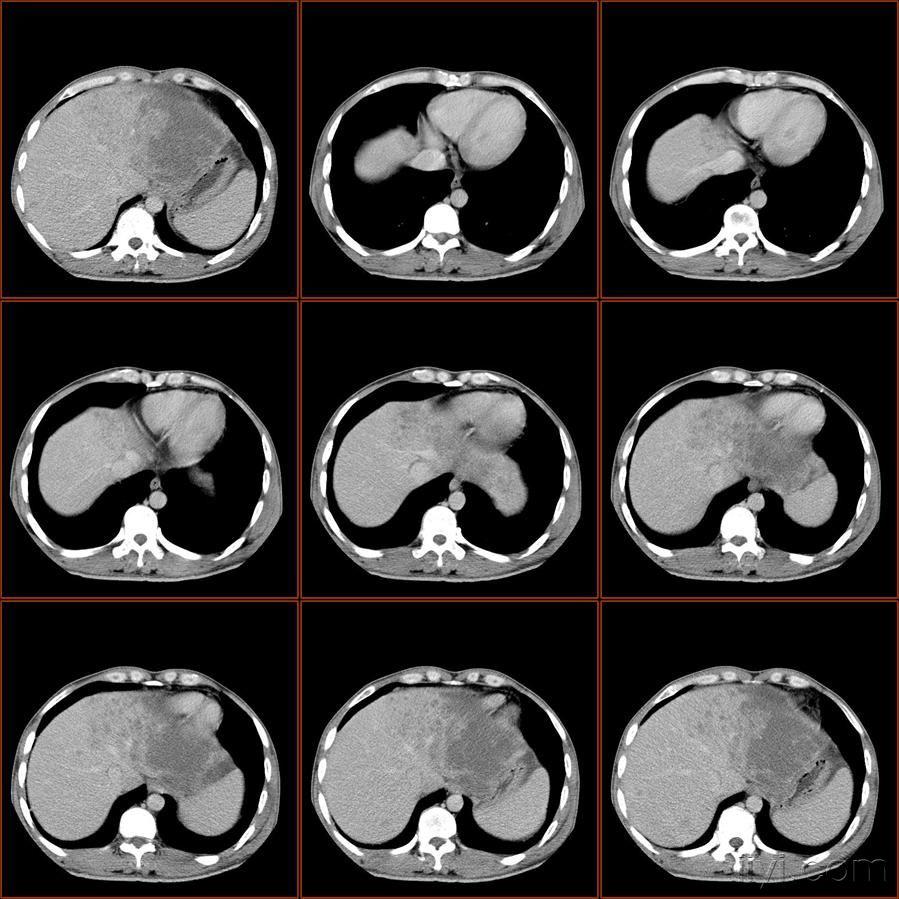

【读片】肝左叶内侧段低密度灶,增强环形强化,病人随访中,请讨论.

ct53402:患者 男 41 肝左叶低密度影.请会诊

肝左叶病变有随访结果已公布随访结果

病例分享各位国青院士莅临指导一下这样的肝左叶区占位性病变您考虑